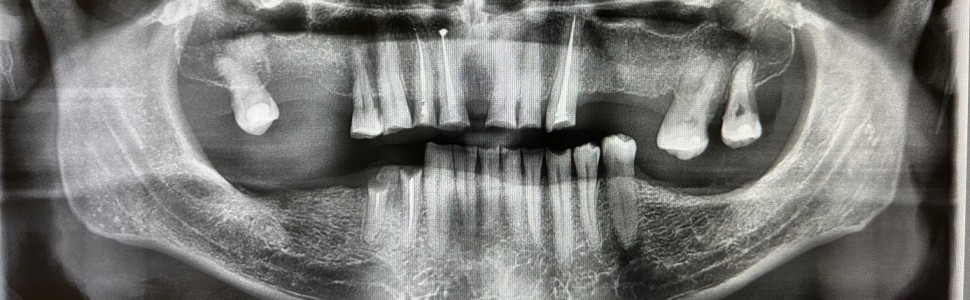

W pracy opisano przypadek pacjenta z obniżoną wysokością zwarcia z zaburzonym przebiegiem płaszczyzny protetycznej, u którego rehabilitację protetyczną wykonano dwuetapowo z wykorzystaniem pracy kombinowanej będącej połączeniem elementów protetyki stałej i ruchomej. Rekonstrukcja protetyczna narządu żucia przywróciła pacjentowi prawidłową relację przestrzenną żuchwy, dając satysfakcjonujący efekt estetyczny i poprawę funkcji.

This paper describes the case of a patient with reduced vertical dimension of occlusion and a disturbed occlusal plane. Prosthetic rehabilitation was performed in two stages using a combined approach combining fixed and removable dentures. Prosthetic reconstruction of the masticatory system restored the patient's correct spatial relationship of the mandible, providing a satisfactory aesthetic outcome and improved function.